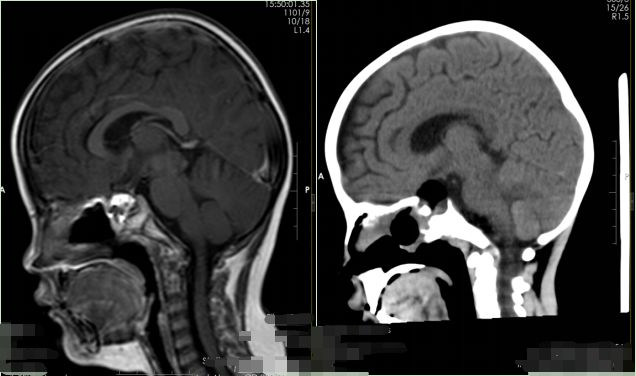

▲术前影像检查

鲁明仔细检查了患儿的影像资料,为明确病情,又为患儿安排了头颅CT检查。结合临床病症,最终患儿被诊断为颅咽管瘤。目前肿瘤已经损害到患儿的垂体功能,导致皮质醇下降。鲁明立即联系了肿瘤科、内分泌科和放射科的多位专家进行联合会诊,经过讨论分析,一致认为应先补充患儿的激素再进行手术。

▲术后影像检查

术后复查MR显示患儿的肿瘤已被全部切除。配合专科治疗及护理后,目前毛大哥的女儿已经顺利出院。